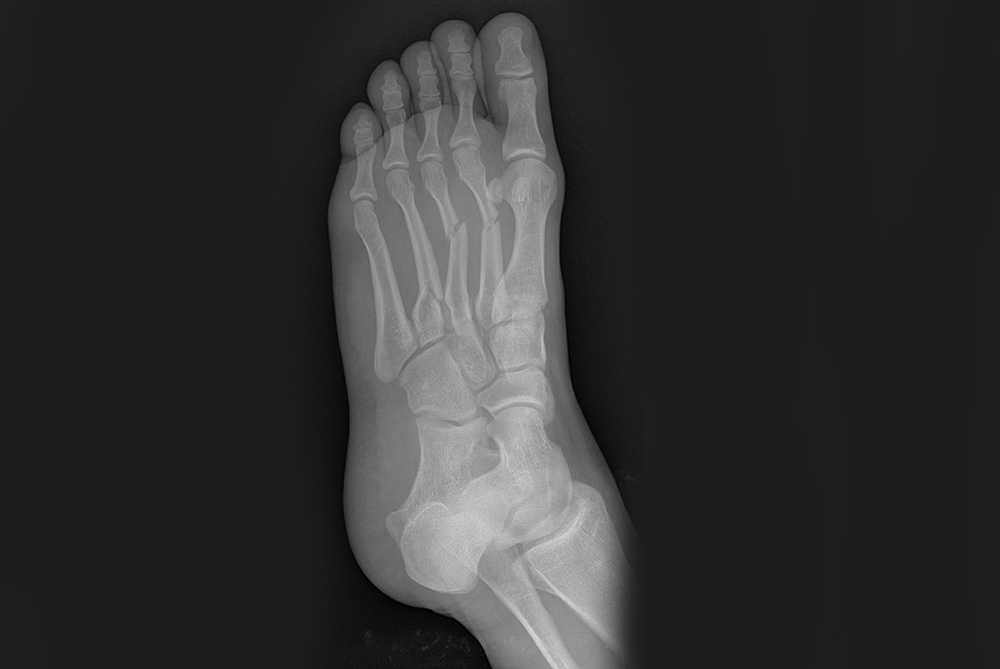

Złamanie kości śródstopia

Złamania kości śródstopia występują dość rzadko. Zazwyczaj są wynikiem urazu bezpośredniego, takiego jak upadek ciężkiego przedmiotu na stopę lub urazów w wypadkach komunikacyjnych. Mogą być również wynikiem kopnięcia stopą w twardy, ciężki przedmiot. Leczenie złamań kości śródstopia zależy od stopnia przemieszczenia odłamów oraz stanu okolicznych tkanek miękkich i uszkodzeń towarzyszących. Często złamania II, III oraz IV kości śródstopia są nieprzemieszczone, wtedy mogą być leczone unieruchomieniem kończyny w opatrunku gipsowym. Gorsza sytuacja jest ze złamaniami trzonu V kości śródstopia, które zazwyczaj wymagają operacyjnego nastawienia odłamów i ich zespolenia. Leczenia operacyjnego wymagają zazwyczaj również złamania kilku kości śródstopia. Złamania I kości śródstopia są wyjątkowo rzadkie i ich wystąpienie wymaga bardzo dużej energii urazu. Z reguły wymagają leczenia operacyjnego.